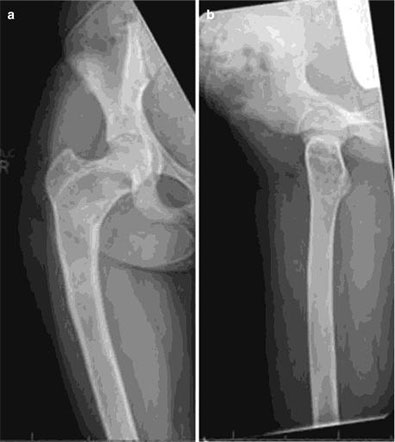

Опухоли костей являются редкими поражениями. Большая часть таких опухолей - доброкачественные образования, которые часто обнаруживаются случайно при радиологических исследованиях, проводимых по другим причинам. Что касается жалоб, они обычно проявляются отеком и болью. В редких случаях они обнаруживаются вследствие вызванного ими перелома в месте их расположения. Наиболее часто встречающимися доброкачественными образованиями являются остеоид-остеома, остеохондрома (экзостоз), энхондрома, неоссифицирующая фиброма, эозинофильная гранулема, простая костная киста, фиброзная дисплазия и внутрикостная липома / ганглия.